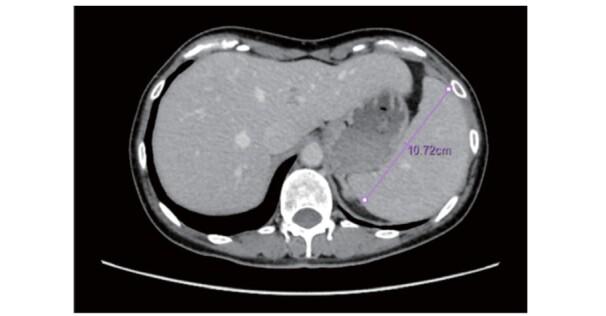

Tangier 病是一种遗传性疾病,其特征是高密度脂蛋白(HDL)-胆固醇(HDL-C)水平极低或完全缺乏。该病由载脂蛋白转运体 A1(ABCA1)基因突变引起,该基因对于细胞内胆固醇和磷脂向 HDL 颗粒的转化至关重要,呈常染色体隐性遗传模式。迄今为止,日本共报道了 35 例 Tangier 病,国外共报道了 109 例。ABCA1 基因两个等位基因突变(纯合子或复合杂合子)的患者,HDL-C 水平通常<5mg/dL,载脂蛋白 A-I(apoA-I)水平<10mg/dL,apoA-I 是 HDL 的主要蛋白成分。Tangier 病患者的主要体征包括:咽扁桃体橘黄色、肝脾肿大、角膜混浊、淋巴结肿大和周围神经病变。尽管患者的 LDL-C 水平通常较低,但仍易发生早发冠心病。目前尚无特效治疗方法,因此早期识别患者并预防动脉粥样硬化的发生至关重要。除了治疗低 HDL-C 外,还应重视 LDL-C 水平、高血压和吸烟等其他危险因素的管理。此外,由于偶尔会出现胰岛β细胞分泌胰岛素受损的情况,因此可能需要治疗葡萄糖耐量异常。